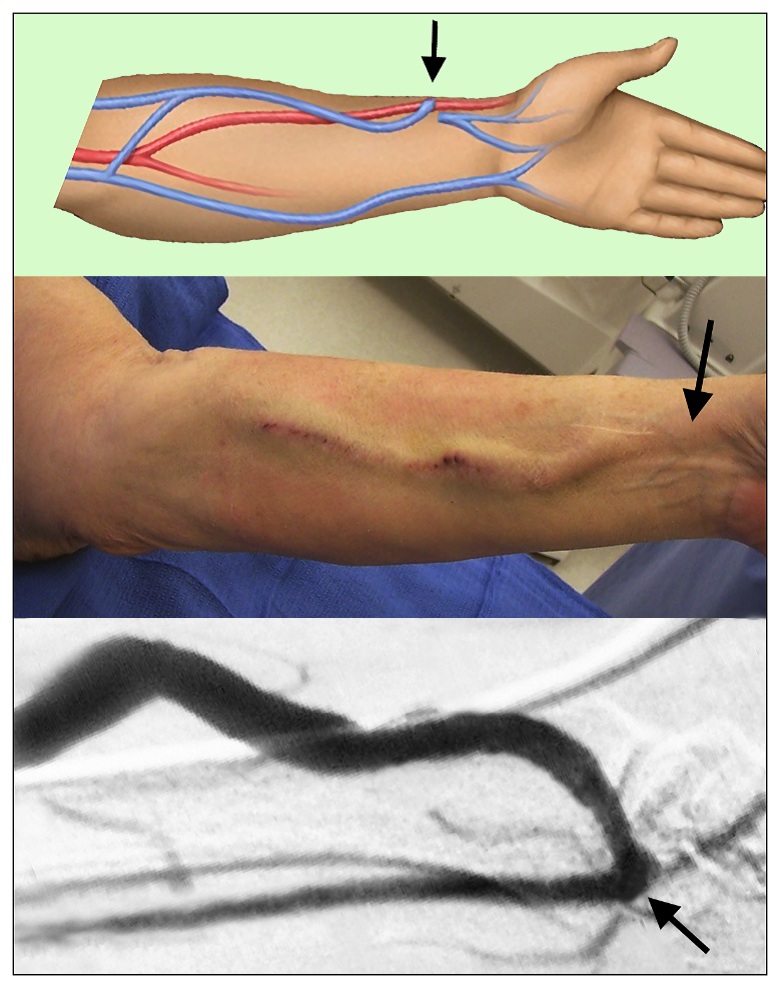

Figure 1

Figure text